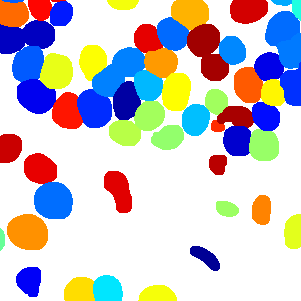

As an essential part of digital pathology, histopathology image analysis is playing increasingly important role in cancer diagnosis, which can provide direct and reliable evidence to diagnose the grade and type of cancer. This paper deals with nuclei segmentation, an important step in histopathological image analysis. The purpose of nuclei semgentation is not only counting the number of nuclei but also obtaining the detailed information of each nucleus. So unlike nuclei detection, here the outputs are the contour of each nucleus instead of only the position of their central points. Hence we can exactly extract each nucleus from the image and make it available for further analysis. For example, the features of the individual nucleus and the distribution of nuclei clusters can be used to grade and classify status of breast cancers [3, 4]. Because of appearance variation such as color, shape, and texture, nuclei segmentation from histopathological images could be very challenging, as illustrated in Fig.1, in which it is very challenging even for human to recognize and segment all nuclei within the images. Fig.1(a) and Fig.1(b) illustrate two histopathological images from different organs. Fig.1(c) and Fig.1(d) are two histopathological images from same organ but have different cancer grade.